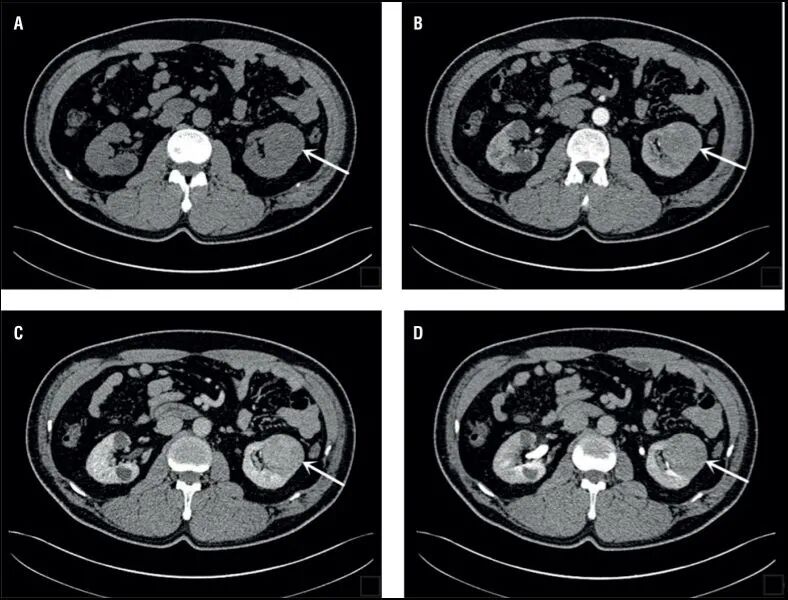

CT图像举例

dr在彩超什么意思一文搞懂X线、CT、MR、彩超检查的区别_https://www.jmylbn.com_新闻资讯_第13张

dr在彩超什么意思一文搞懂X线、CT、MR、彩超检查的区别_https://www.jmylbn.com_新闻资讯_第14张

CT检查相当于把人体切成一定间距的小段,间距可以是0.25cm、0.5cm、1cm等等,切完以后可以在图像上看到一段横切面的状态。不同的切面呈现不一样的脏器,通过扫描把人体各个部位的器官和结构拉开,使我们可以看得非常清晰。

擅长神经系统、心脏大血管疾病

可以断层看,经后期处理可以显示更多信息;

辐射剂量高;